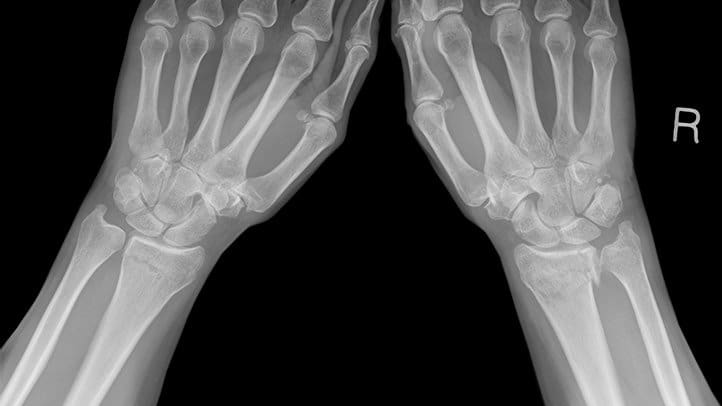

Pemindaian tulang yang dilakukan dengan menggunakan teknologi modern memungkinkan untuk mendeskripsikan penyakit yang dikenal dalam dunia medis sebagai “osteoporosis,” atau pengeroposan tulang.

Osteoporosis adalah penyakit metabolik tulang yang mempunyai sifat-sifat khas berupa massa tulang yang rendah, disertai mikro arsitektur tulang dan penurunan kualitas jaringan tulang yang dapat akhirnya menimbulkan kerapuhan tulang. Kata osteoporosis berasal dari kombinasi kata osteo (tulang) dan porosis (penuh lubang).

Untuk melihat gangguan pada tulang maka kita membutuhan bantuan X-Ray, mengingat bahwa x-ray hanya ditemukan pada tahun 1890, jelas betapa sulitnya mendapatkan informasi apapun mengenai tulang pada waktu itu.